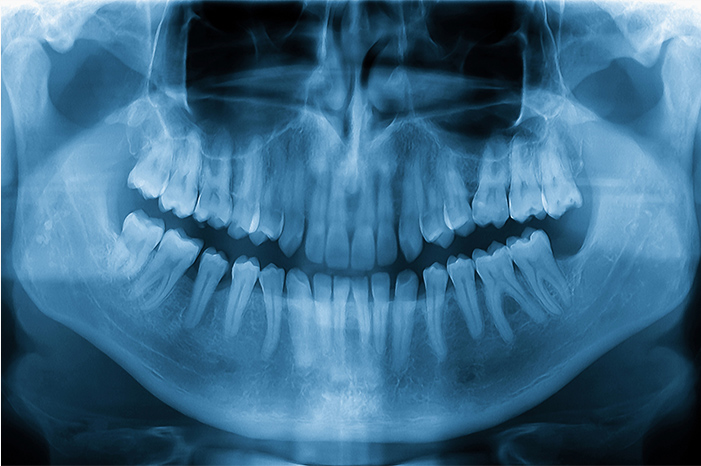

歯科用CT

歯や骨の内部構造を立体的に確認できる歯科用CTを使用し、根管の形や感染の広がりを正確に把握します。見えにくい部分まで把握することで、再発を防ぐ精密な治療につなげています。